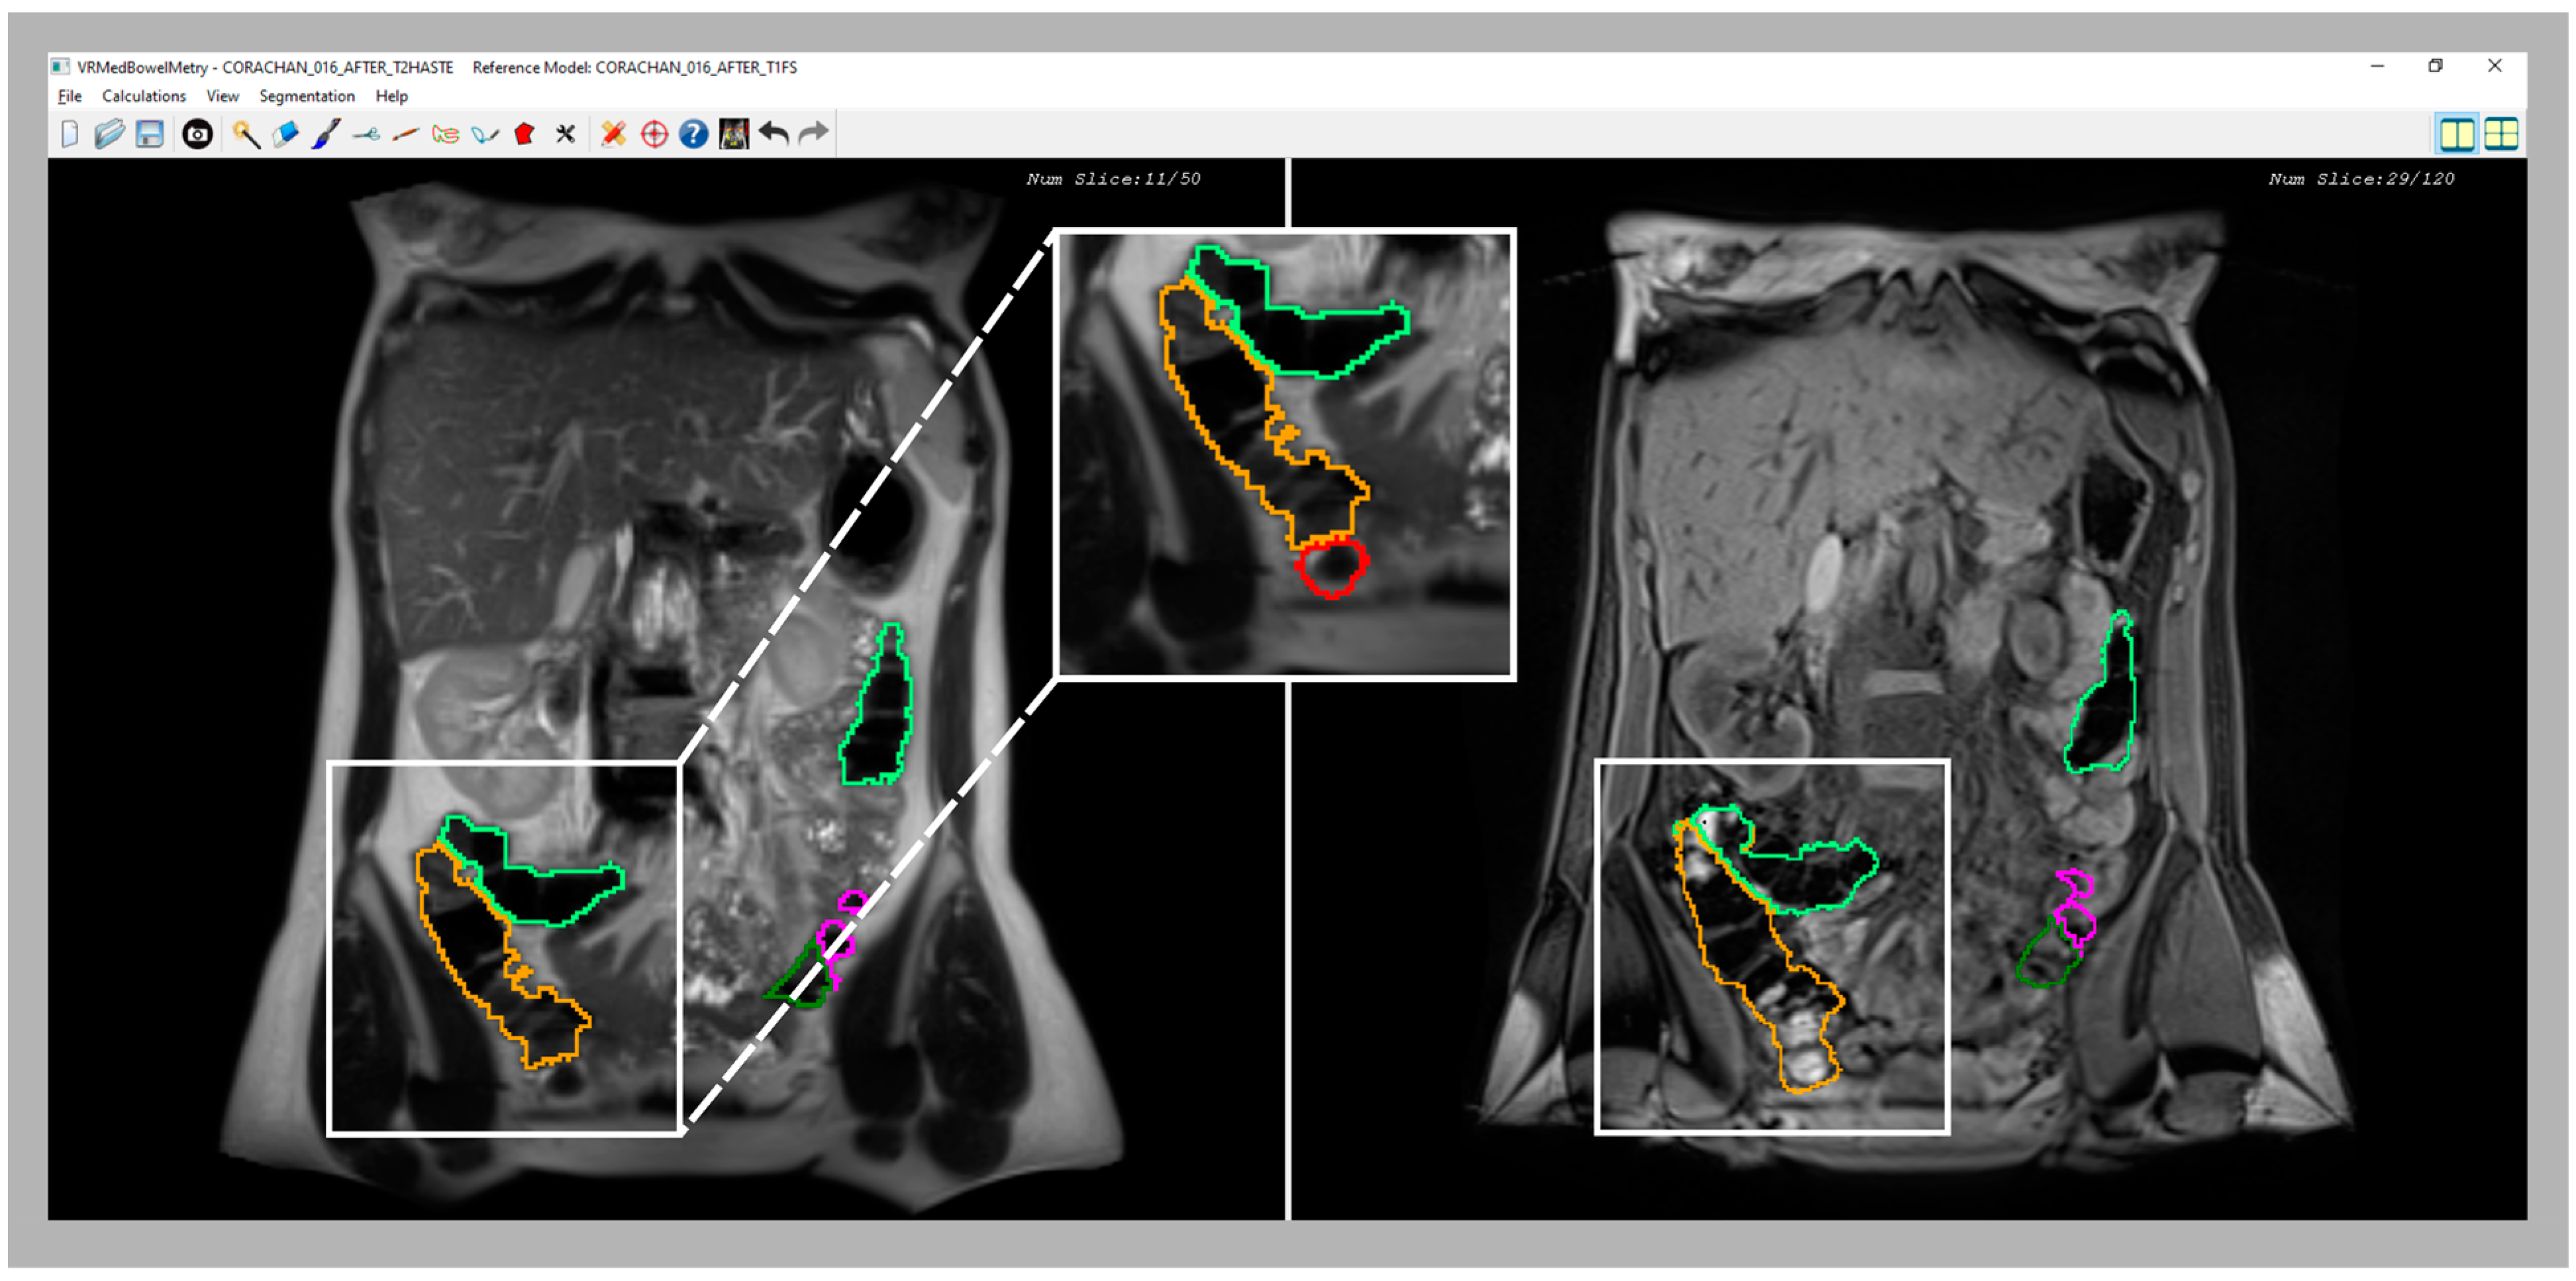

Figure 6.

Comparative images of a confusing area of the cecum in T2 (left image) and T1-FS (right image) sequences. Note that in the T2 sequence, part of cecum was not included in the initial segmentation because it was confused with the small bowel; a zoom (central image) provides a better visualization of the non-included area (red line). However, in the synchronized visualization with the T1 sequence (right image), the feces facilitate the cecum demarcation. Therefore, using the new inspection module, the medical specialist should be able to correct and include the cecum in the final segmentation.

As shown in previous sections, a synchronized visualization of T1-FS and T2 sequences is required to validate the coherence between both colon segmentations and, also, to correct the results in some confusing zones (see an example in Figure 6).

The validation of this module consisted of the visual analysis of some colon segmentation results by medical experts. We specially chose those cases where the isolated validation of T2 and T1-FS segmentation showed some small differences.

In all the analyzed cases, when the specialist detected a complex area where the colon was difficult to identify using only one sequence (T2 or T1-FS), the analysis of the same area in the other sequence helped him to decide. In general, these confusing areas were located in the T2 images, especially where the small intestine was very close to the colon and their pixel intensities were similar (see Figure 6). The new module facilitates and gives security to the specialists at the time of determining the belonging of the area to the colon. Another complex area was the liver zone, where sometimes the separation between the colon and the liver is not clear enough to determine, accurately, the separation between both anatomical structures. The use of the synchronized navigation helped the specialist to be confident in this decision.